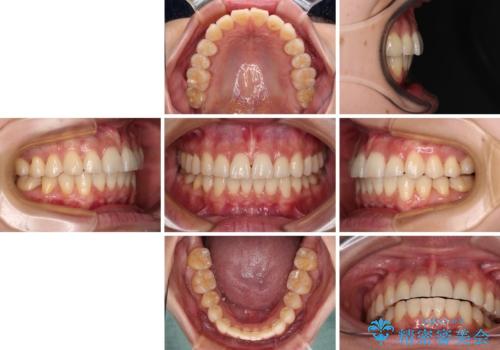

前にずれた咬み合わせをワイヤー装置でしっかりと改善

奥歯の咬み合わせは理想的な状態に改善され、その結果として上下歯列もバランスの良い位置に収めることができました。

若干ではあるものの上顎前歯を内側に移動させることができ、以前よりも口が閉じやすいと感じるようになりました。